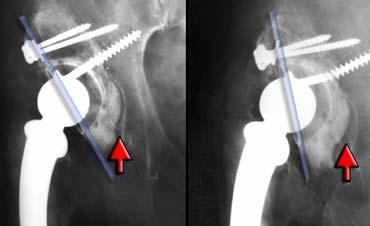

Di lệch cấu phần có giá trị chẩn đoán tình trạng lỏng khớp.

Biểu hiện là sự nghiêng hoặc di lệch lên trên của ổ cối nhân tạo, hoặc sự lún xuống (>10mm) và nghiêng varus của cán khớp háng.

Trường hợp bên trái cho thấy tình trạng lún xuống tiến triển, có giá trị chẩn đoán tình trạng lỏng khớp, kèm theo gãy vít tiếp theo sau đó.

Lỏng khớp (2)

Vì sự di chuyển có thể rất tinh tế, cần so sánh cẩn thận với phim chụp sau phẫu thuật ban đầu.

Không chỉ so sánh với lần khám trước đó.

Trường hợp bên trái cho thấy sự di chuyển của chỏm acetabulum, điều này sẽ được nhận thấy rõ hơn nếu sử dụng một điểm tham chiếu (xem hình tiếp theo)